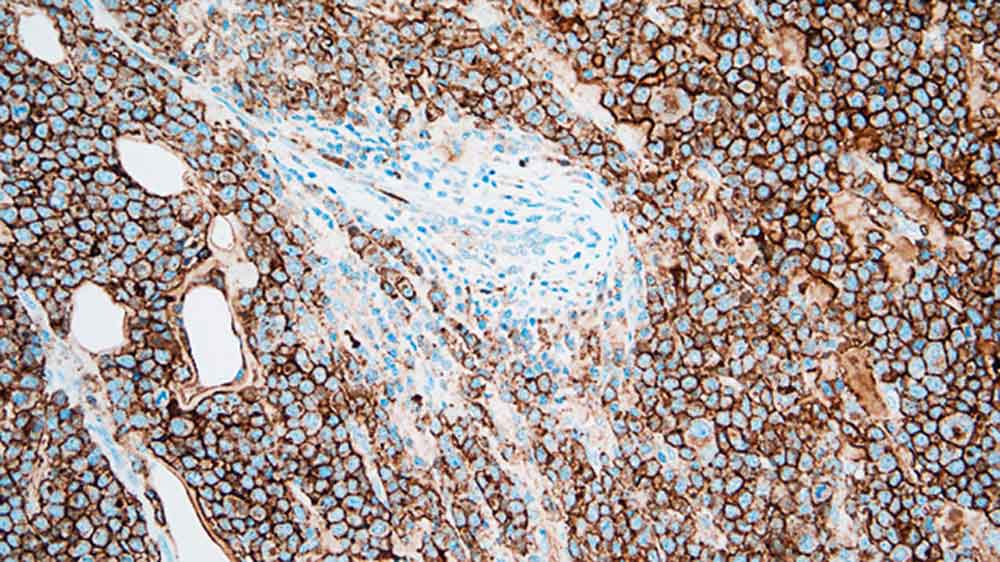

Plasmacytoma: immunohistochemical staining for CD138. Note the intense membrane staining of tumor cells. CD138: clone MI15

The CD138 molecule is a transmembrane heparan sulphate glycoprotein expressed at distinct stages of differentiation in normal lymphoid cells such as pre-B cells, immature B cells and Ig-producing plasma cells as well as being expressed in stratified and simple epithelia. The loss of CD138 expression from atypical cells is reported to be an early event during cervical carcinogenesis whereas CD138 antigen expression shows a close association with preserved epithelial morphology and differentiation; however, the major utility of CD138 as a marker in immunohistochemistry is the quantification of plasma cells.